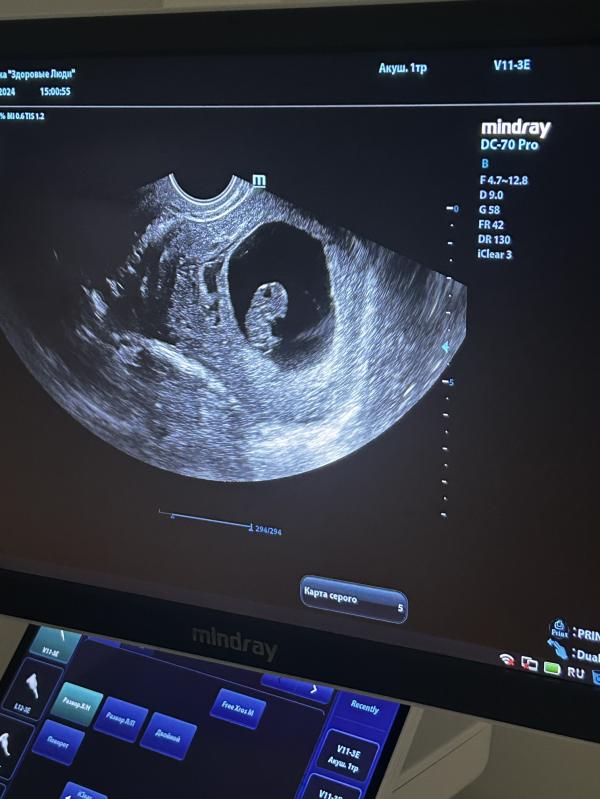

Была сегодня на УЗИ, поставили срок 8 н. 6 дней и дали послушать сердцебиение 💛 Также обнаружили маленькую гематому, но сказали, что в этом ничего страшного нет. Не знаю, как я дожила до этого узи в буквальном смысле. Меня жутко🤮 , была температура, кашель и насморк. Все было как в тумане для меня. Я еле вставала с кровати, все время хотелось спать и ничего не делать. А надо ещё за ребенком первым смотреть, её тоже лечить, в сад не ходит пока. Муж все время на работе…Я поняла, что апокалипсис существует😂